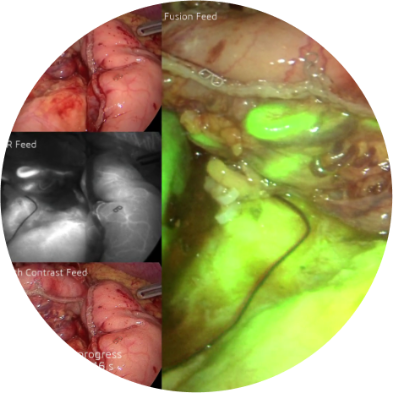

• 4K NIR for advanced procedures requiring fluorescence visualization,